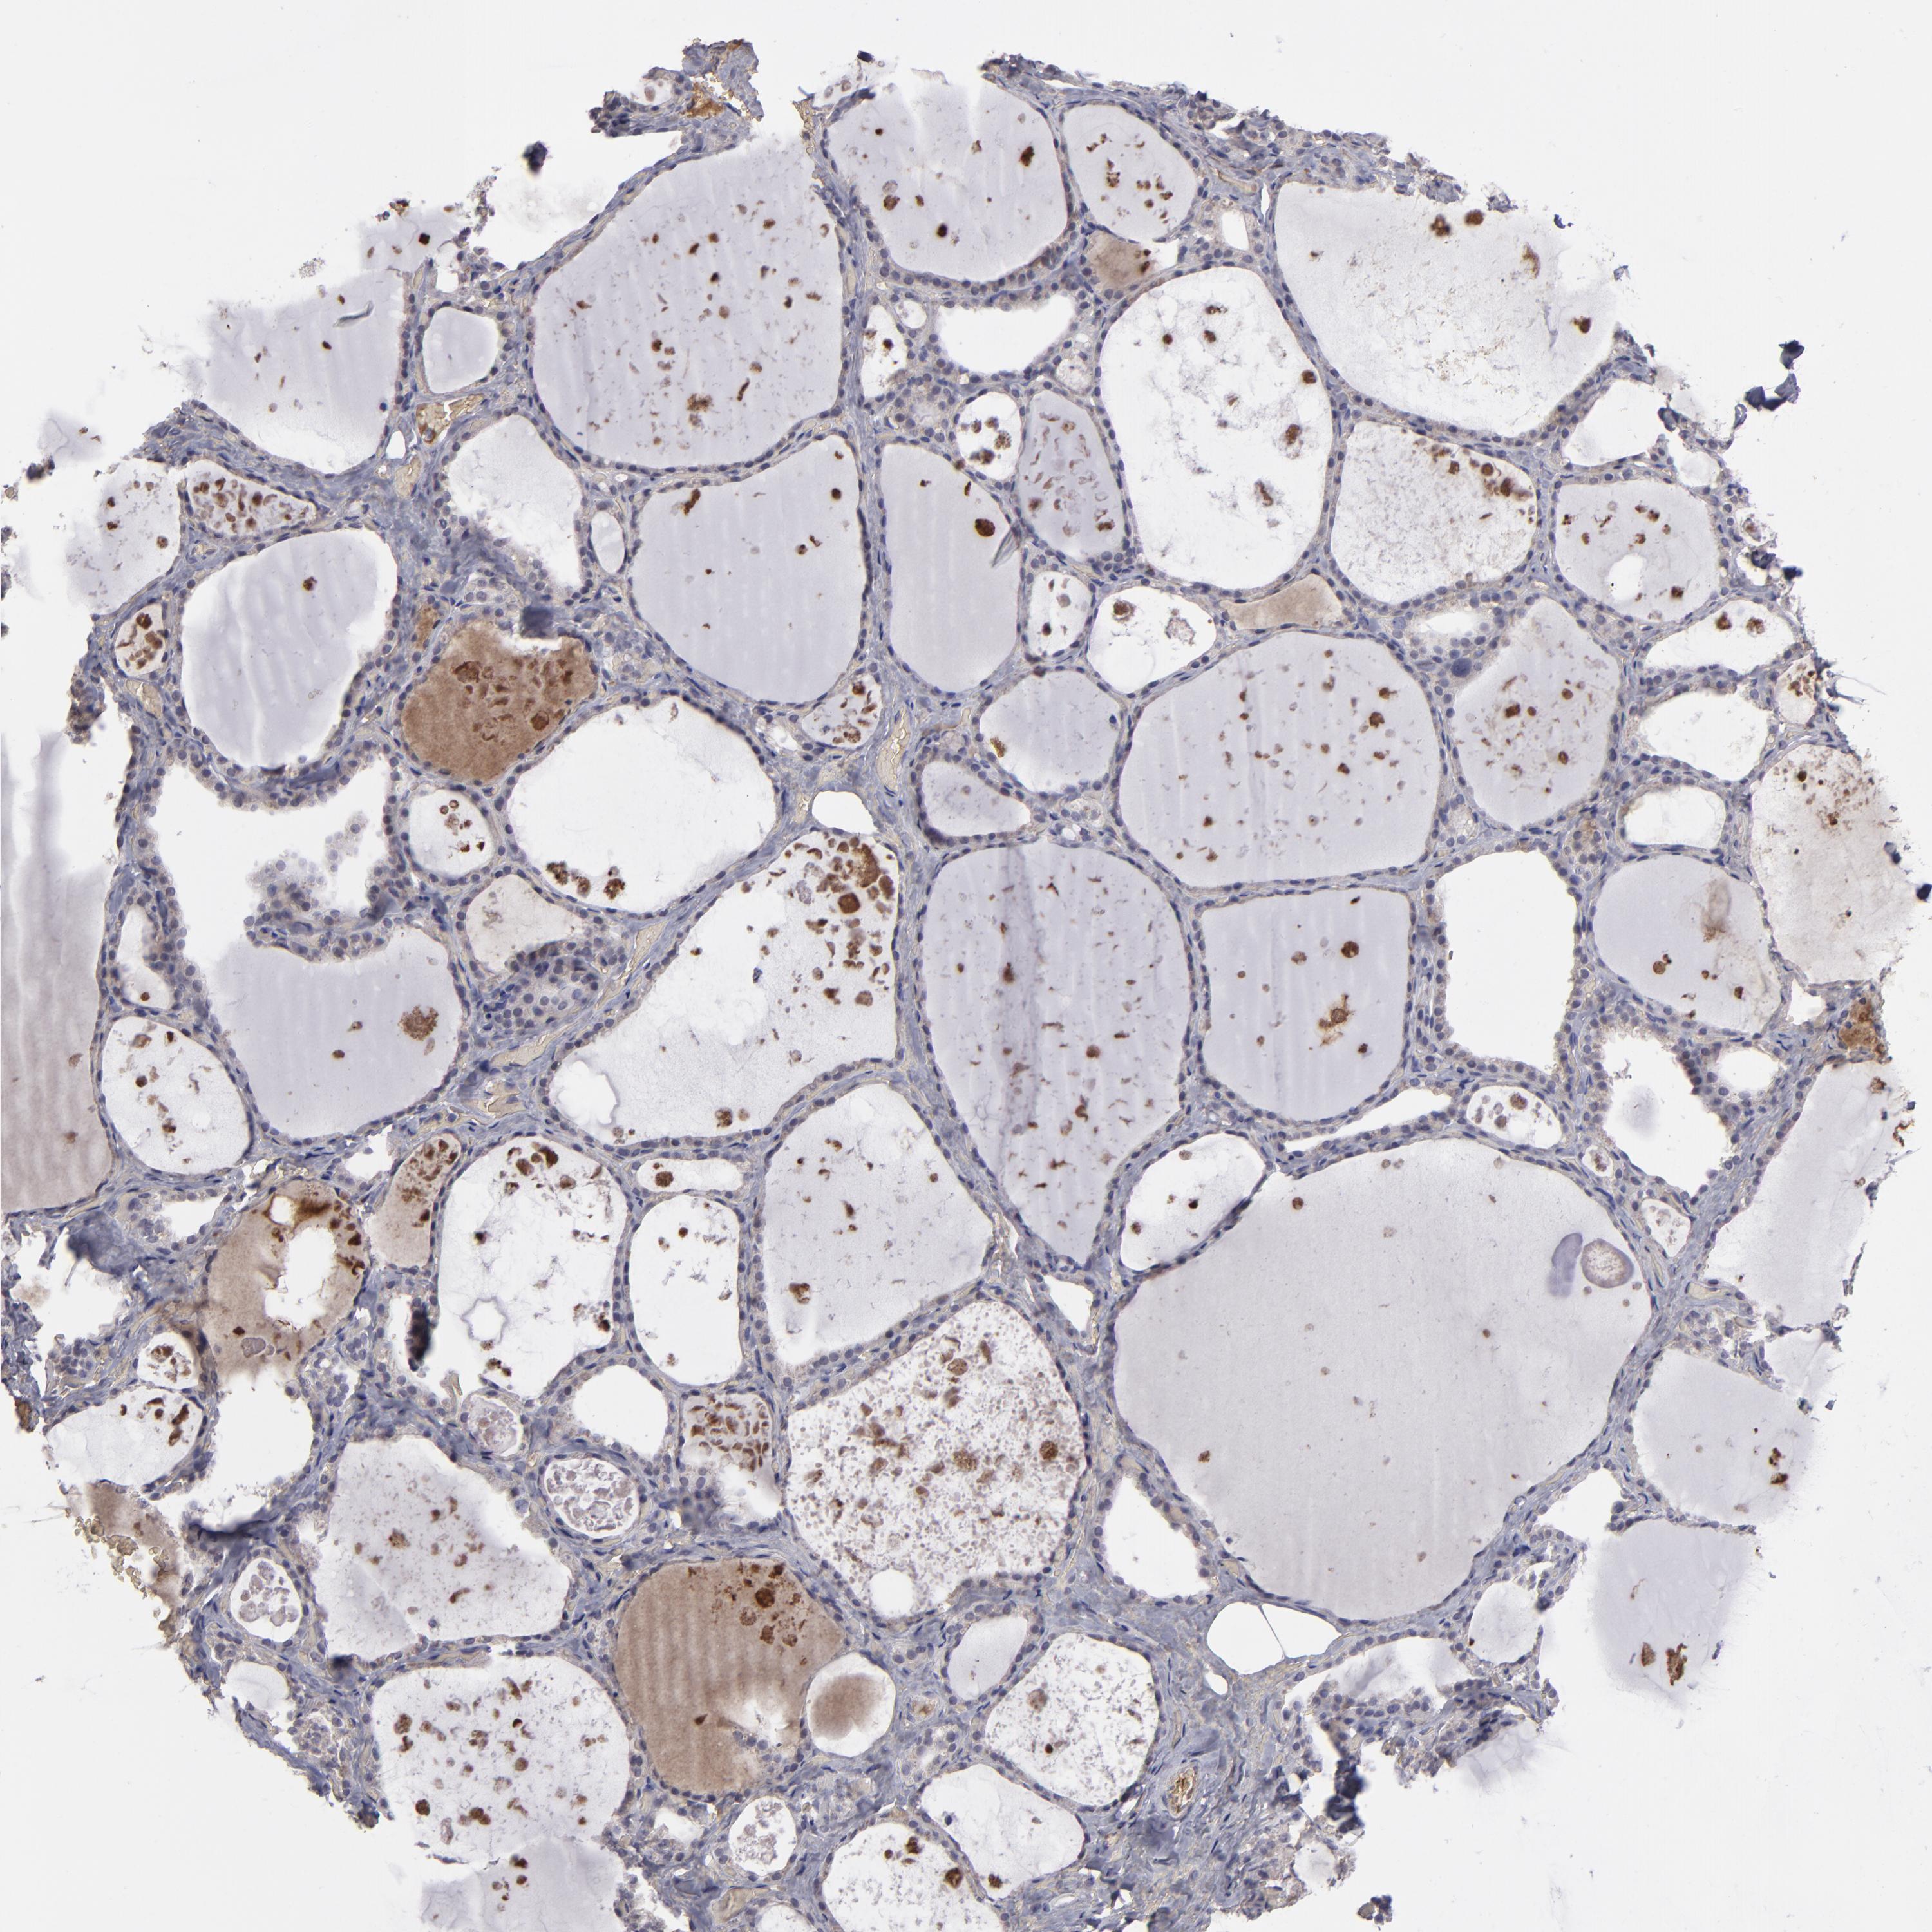

THYROID GLAND - Antibody stainingi

Antibody staining in the annotated cell types in the current human tissue is reported as not detected, low, medium, or high, based on conventional immunohistochemistry profiling in selected tissues. This score is based on the combination of the staining intensity and fraction of stained cells.

Each image is clickable and will lead to virtual microscopy that enables deeper exploration of all samples and also displays staining intensity scores, fraction scores and subcellular localization as well as patient and tissue information for each sample.

Antibody HPA001835Antibody HPA003948Antibody CAB072872

Glandular cells Not detectedNot detectedNot detected